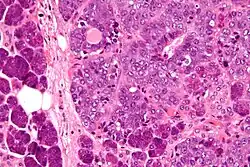

Micrograph of an epithelial-myoepithelial carcinoma (right of image). The epithelial component has a tubular morphology and is evident only focally (upper left of image). Benign serous glands (parotid salivary gland) are also seen (left of image). H&E stain.

This tumour is characterised by biphasic tubular structures composed of inner ductal and outer clear myoepithelial cells.

Its appearance is very similar to adenomyoepithelioma of the breast, which may be the same tumour at a different anatomical site.[3]

The histologic differential diagnosis includes adenoid cystic carcinoma and pleomorphic adenoma.